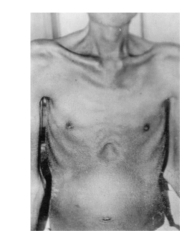

1.4.1.5.1一、症状及体征